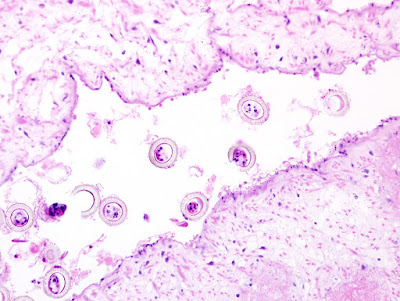

This week's case was generously donated by Bryan Schmitt and Stephanie Kinney at Indiana University. Several specimens measuring approximately 1 cm in length were obtained during routine colonoscopy on a hispanic woman in her 50's; they were mistaken as colon polyps and submitted for histopathology. Identification?

H&E, 20x

H&E, 400x

The striated outer shell is consistent with that of Toenia species ova.

The lateral genital pore and the more than 13 uteral branches is compatible with T. Saginata.

Certainly Taenia sp. due to gross morphology and ova morphology. Taenia saginata would be my best diagnosis due to the number of uteral branches.